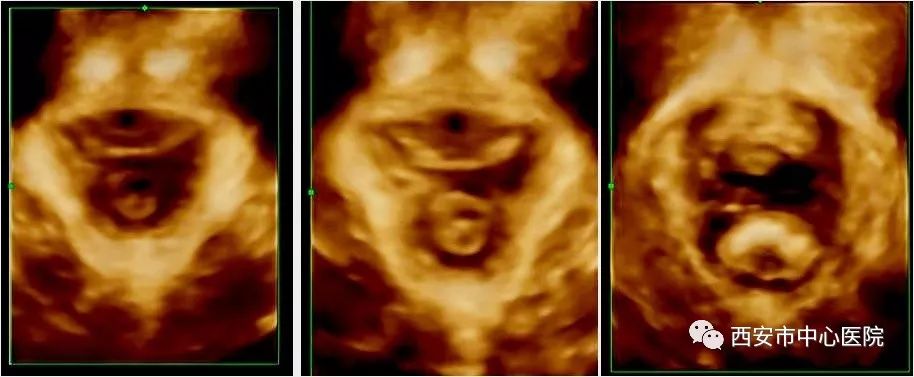

盆底超声包括二维超声检查盆底脏器有无脱垂及盆底四维成像检查盆底肌肉的完整性两部分。检查时将配备无菌保护罩探头放于会阴部,通过实时动态观察,比较患者静息、缩肛和Valsalva状态盆腔脏器结构和位置改变,直观反映子宫、直肠、膀胱等盆底器官的情况,可在临床症状出现之前做出早期诊断,为临床医生制定合理的治疗方案提供有力依据。

可以协助评价盆底功能障碍性疾病的程度;

可以用于盆底手术术后的观察,主要是盆底解剖形态的恢复情况(包括吊带及盆底重建植入补片位置、大小、有无折痕、挛缩、侵蚀等并发症出现。)

总而言之,盆底超声对于盆底疾病(包括压力性尿*禁失**、直肠膨出、子宫脱垂、小肠膨出及肠疝等等)的观察具有非常大的优势,通过盆底超声的检查可以对盆底疾病发生的具体解剖、程度、位置等等均有很好的显示作用。同时,盆底超声在盆底疾病手术术后的动态观察(包括补片、吊带的情况、效果等)、评估均有很大的优势。